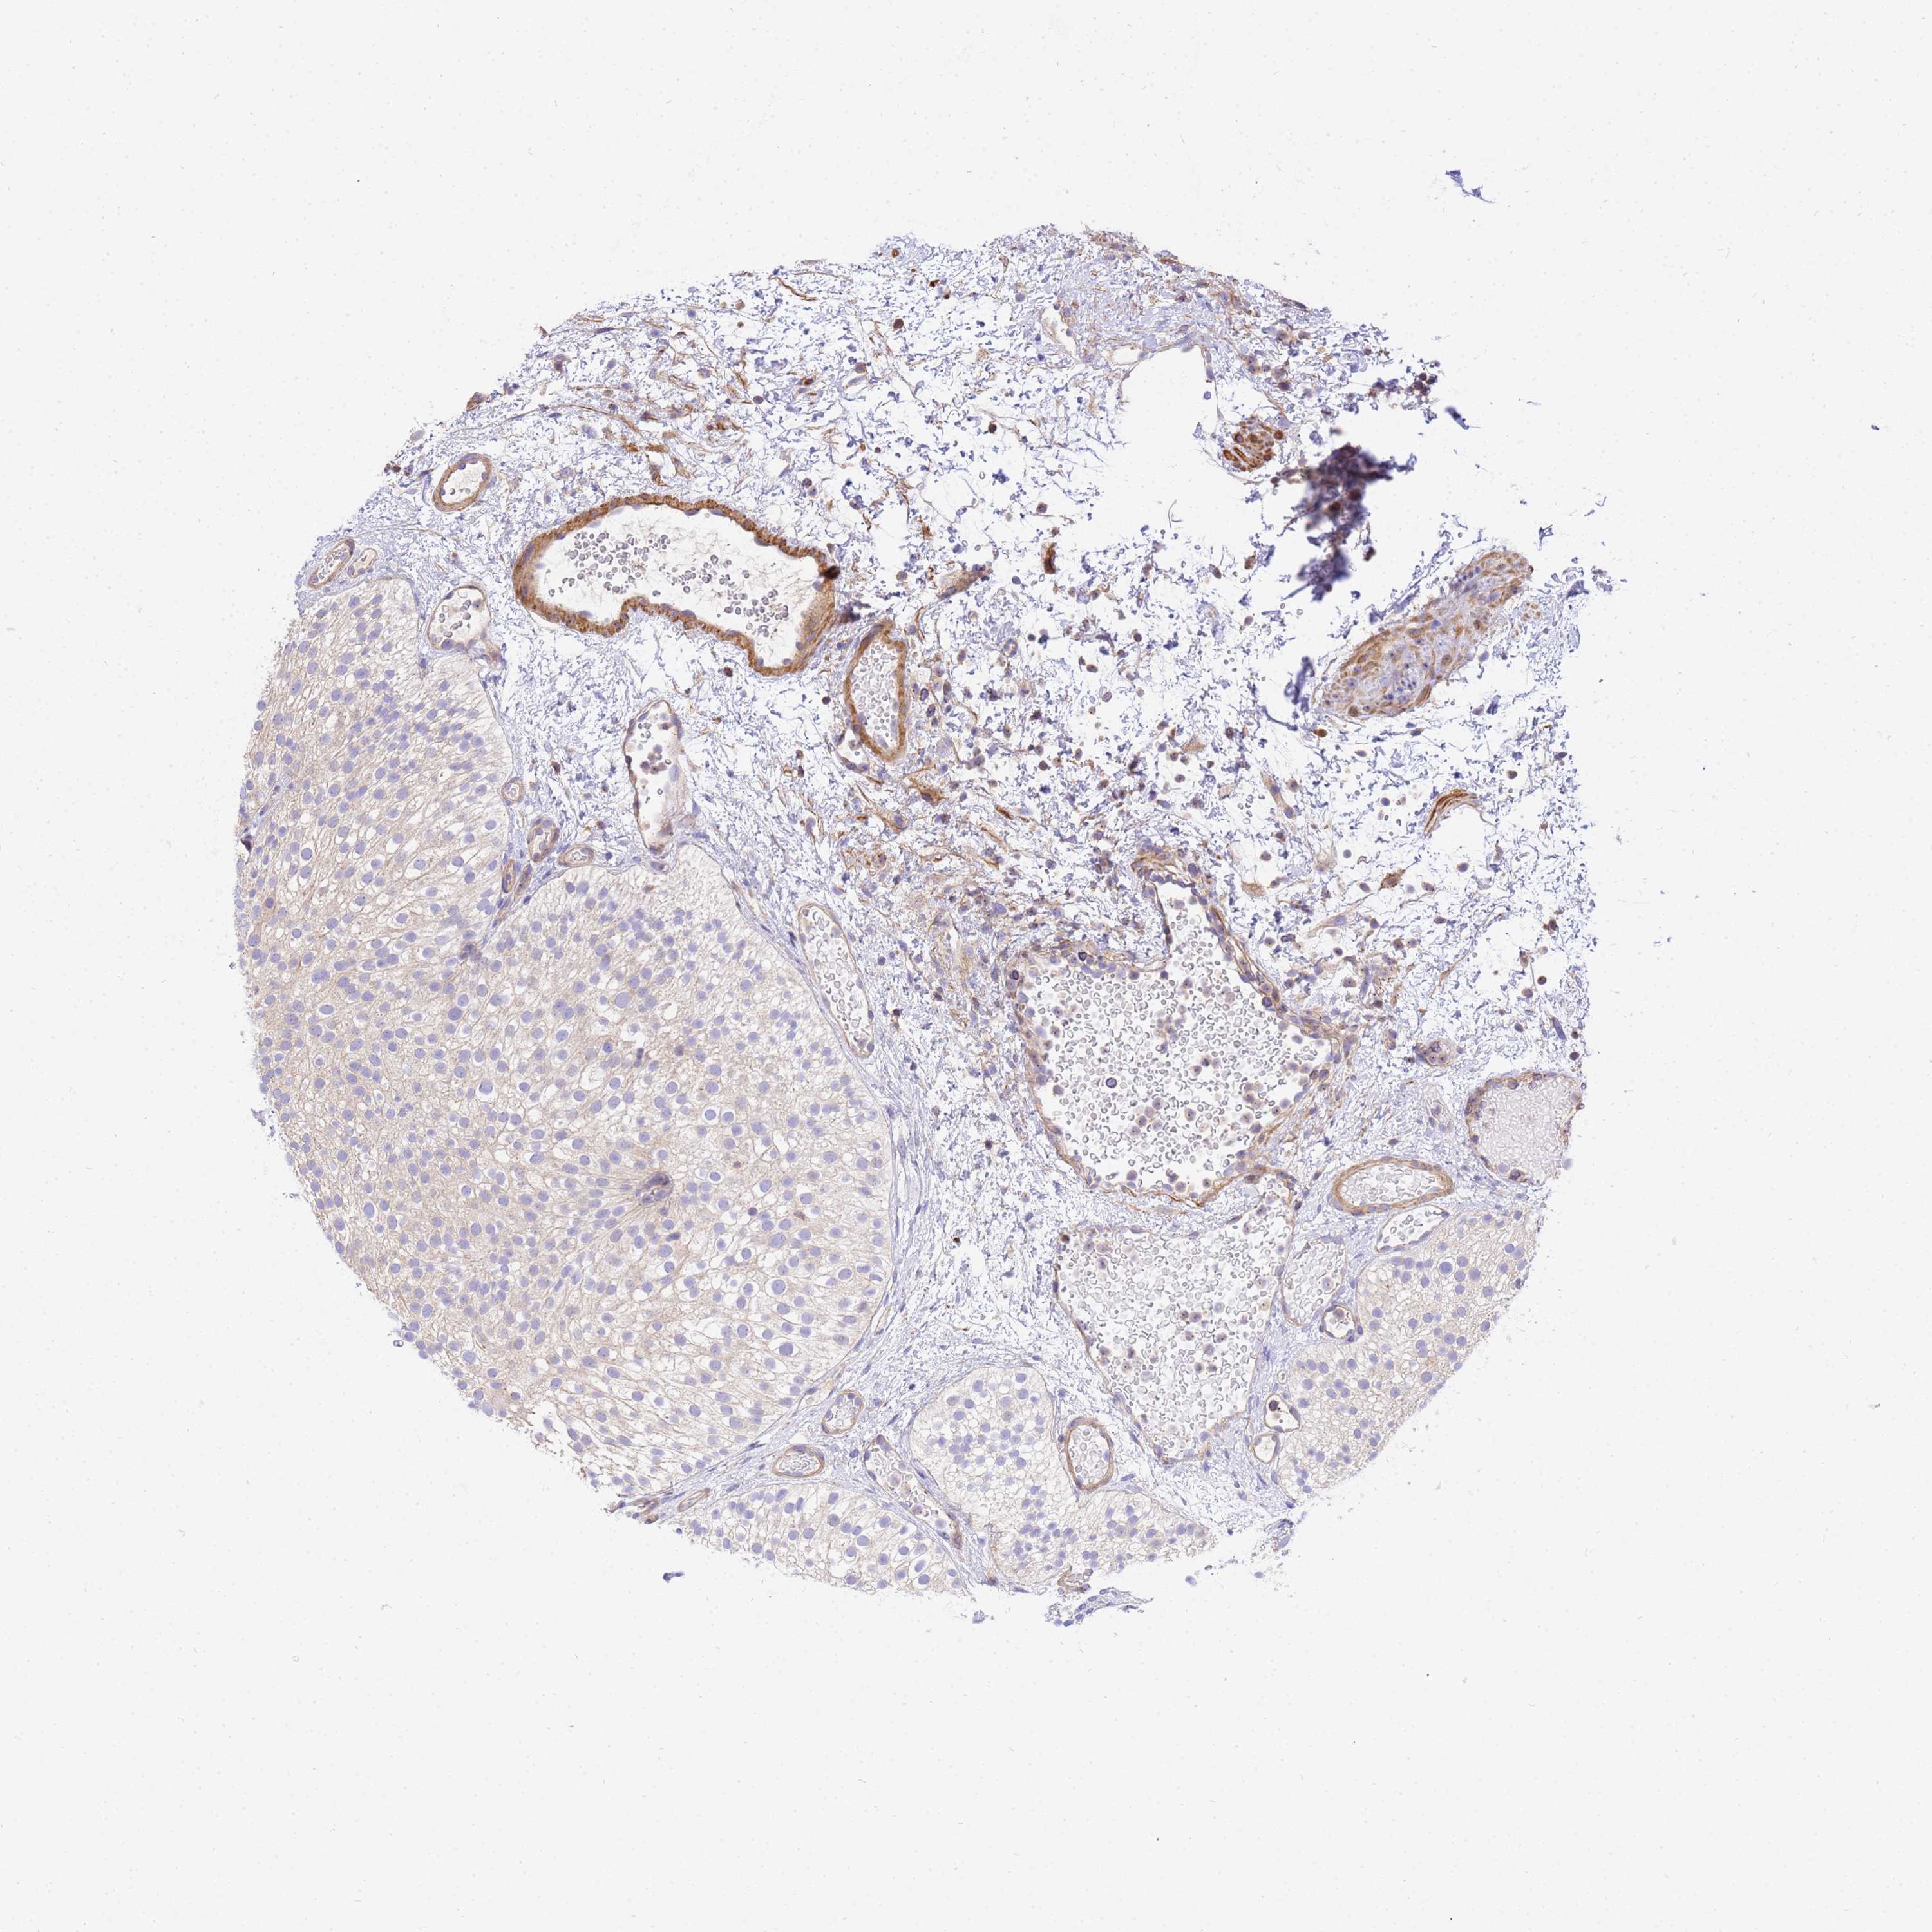

UROTHELIAL CANCER - Protein expressioni

A mouse-over function shows sample information and annotation data. Click on an image to view it in a full screen mode. Samples can be filtered based on level of antibody staining by selecting one or several of the following categories: high, medium, low and not detected. The assay and annotation is described here.

Note that samples used for immunohistochemistry by the Human Protein Atlas do not correspond to samples in the TCGA dataset.

Antibody stainingi

Antibody staining in the annotated cell types in the current human tissue is reported as not detected, low, medium, or high, based on conventional immunohistochemistry profiling in selected tissues. This score is based on the combination of the staining intensity and fraction of stained cells.

Each image is clickable and will lead to virtual microscopy that enables deeper exploration of all samples and also displays staining intensity scores, fraction scores and subcellular localization as well as patient and tissue information for each sample.

Antibody HPA046186

Staining

High

Medium

Low

Not detected

Intensity

Strong

Moderate

Weak

Negative

Quantity

>75%

75%-25%

<25%

None

Location

Nuclear

Cytoplasmic/membranous

Cytoplasmic/membranous,nuclear

Urothelial carcinoma, High grade

Urothelial carcinoma, Low grade